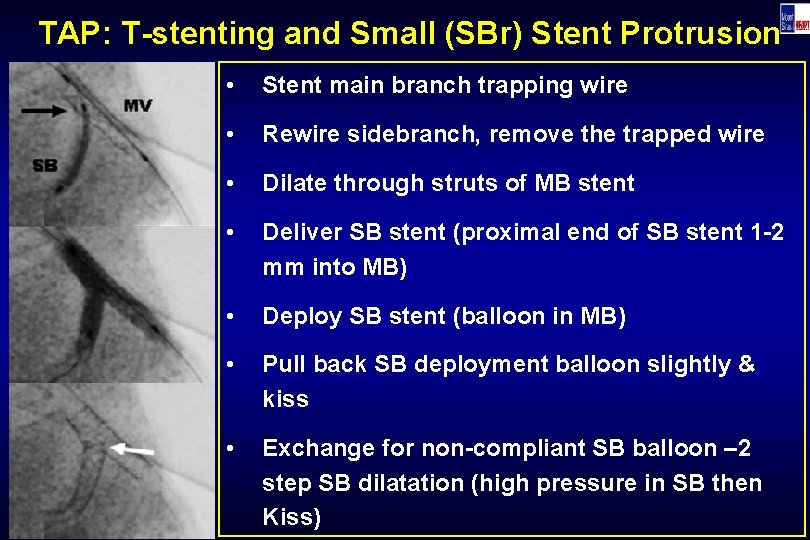

TAP: T-stenting and Small (SBr) Stent Protrusion • Stent main branch trapping wire • Rewire sidebranch, remove the trapped wire • Dilate through struts of MB stent • Deliver SB stent (proximal end of SB stent 1 -2 mm into MB) • Deploy SB stent (balloon in MB) • Pull back SB deployment balloon slightly & kiss • Exchange for non-compliant SB balloon – 2 step SB dilatation (high pressure in SB then Kiss)